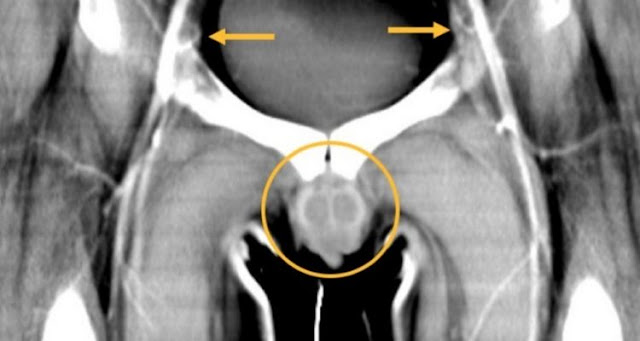

| X-ray performed before the patient's operation. | Redett et al./NEJM |

Yet none of these patients had lost as many elements as this soldier. As a result, his operation was particularly ambitious, involving the transplantation of a single piece of tissue including the penis, scrotum and lower abdominal wall: what the doctors had never tried before!

In total, the entire graft weighed more than two kilograms and was approximately 25 centimeters. Despite the challenges of assembling hundreds of small blood vessels a millimeter or two wide under a powerful microscope, the 14-hour operation, performed by 11 different surgeons, was a success.